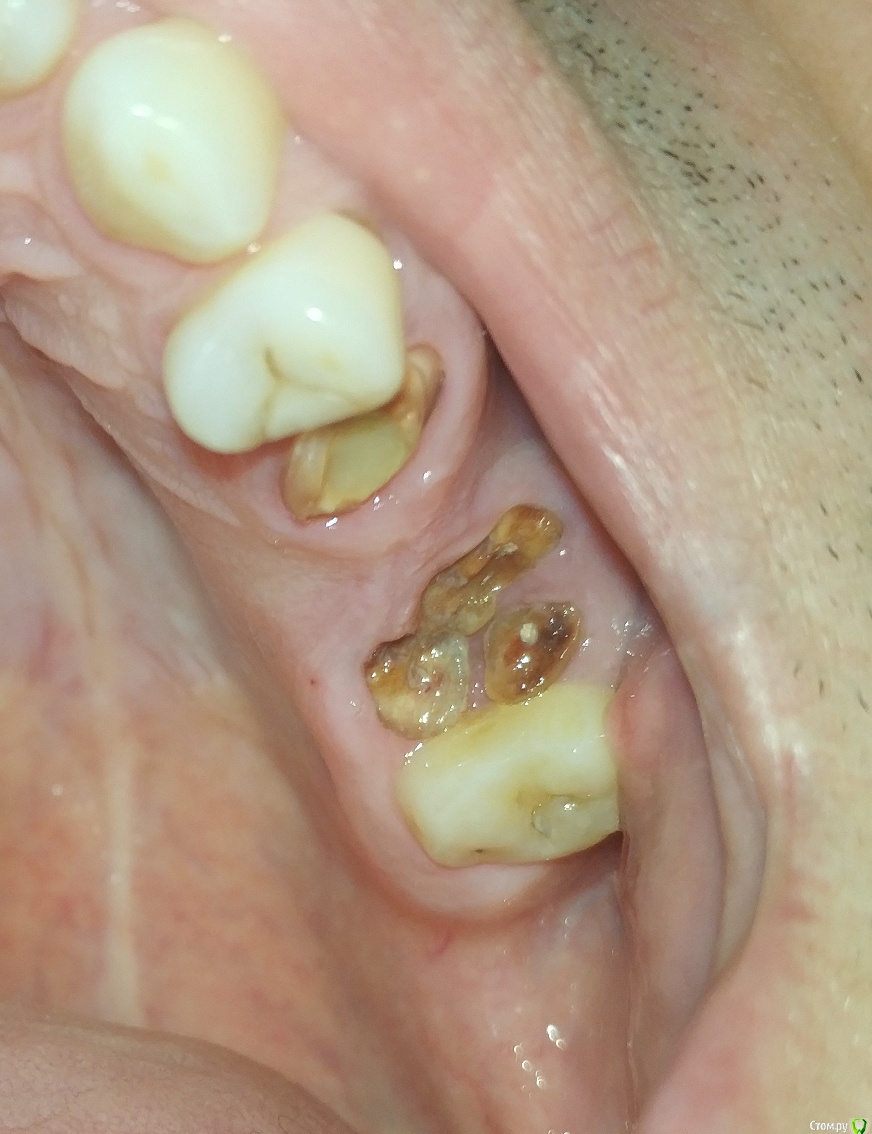

LTD Опубликовано 12 апреля, 2019 Поделиться Опубликовано 12 апреля, 2019 Мужчинка, 45 годов Слетел верхний мост 5-7 . Корень 7 (основание зуба ) отделился / разделился. «Целые» зубы 4, 8 не хочу трогать (обтачивать), решение зависит от бюджета. Просьба высказать мнение :а) Без имплантологии1 - делается ли вкладка на 7ку под дальнейший мост в таком состоянии? 2 - какие варианты восстановления возможны (съемные, бюгель и тд)?3 - какие варианты восстановления наиболее практичны по Вашему? б) хотя имплантация пока не по зубам Хочу понять:3 - на противоположной стороне 7-8 удачно стоит МК консоль на одном 7 зубе. Делается ли имплант с такой же конструкцией консоли на один 7-мой (который разрушен)?4 - делается ли одноэтапная имплантация на 7?5 - имеет ли смысл не удалять корни 7го с этой целью?6 - если 7 имплант + 567 мост (ставится ли мост - конструкция на 5й "свой") ?7 - возможность установки 7 без открытого лифта? Заранее спасибо! Ссылка на комментарий

chervoncevdaniil Опубликовано 12 апреля, 2019 Поделиться Опубликовано 12 апреля, 2019 7 удаление точно и в случае ее удаления установка 2х имплантология в позиции 6-7(если 5 удастся сохранить)Варианты со съёмным протезированием конечно возможны,но маловероятно что вы будете носить съемный протез на 2 зуба 6 Ссылка на комментарий

Doc Опубликовано 13 апреля, 2019 Поделиться Опубликовано 13 апреля, 2019 Копите деньги на имплантацию. Как накопите - семерку удалять и два имплантата. Если пятерка годная, то ее под коронку. Если нет, то удалять и все равно два имплантата, только мостом. Консоль здесь делать нельзя. Перегрузка слишком большая будет, потеряете имплантат. 1 Ссылка на комментарий